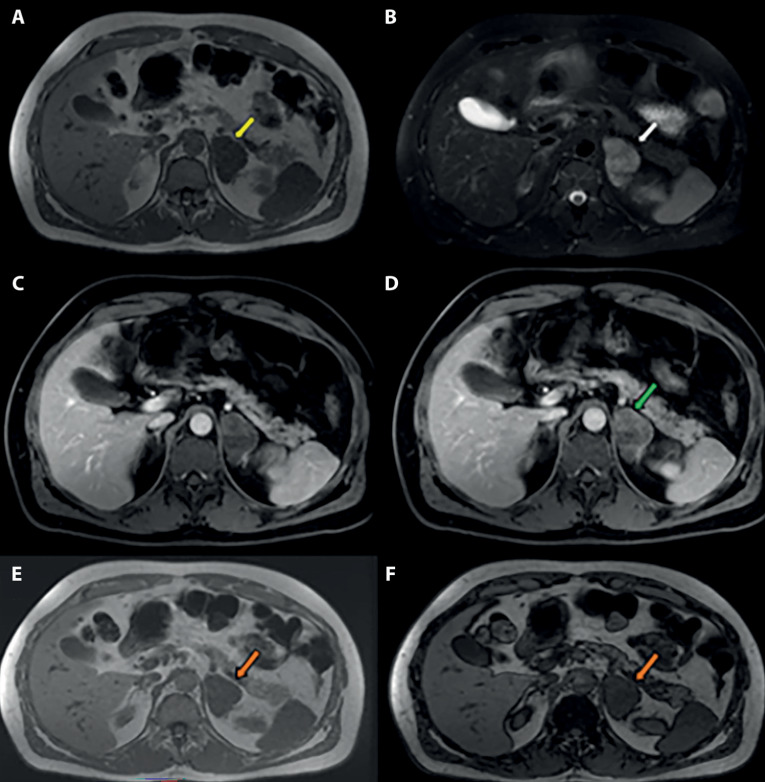

A 53-year-old man complaining of pain in the right hypochondrium underwent an abdominal ultrasound that showed a left adrenal lesion. Further instrumental investigations (CT and MRI, both with contrast medium) were performed which diagnosed an adrenal ganglioneuroma, confirmed by the histological examination. The patient also underwent an endocrinological examination. The treatment was surgical and consisted of an adrenalectomy through video-laparoscopic access. Adrenal ganglioneuromas are rare tumors but well described and known in the literature. For this reason, this case report has primarily an educational purpose: the totality of the data collected (clinical, laboratoristic, instrumental, and histopathological) constituted a multidisciplinary case, with the focus on imaging.